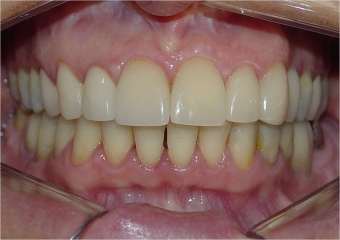

Mordida final